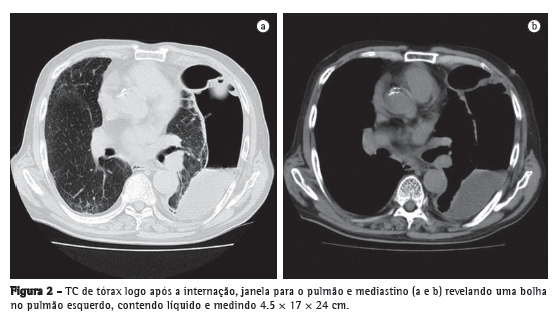

Relato de casoUm homem de 79 anos de idade buscou tratamento no pronto-socorro devido a um histórico de 3 meses de febre persistente, dor torácica e fadiga geral. Apresentava carga tabágica de 60 anos-maço e fizera uso pesado de saquê japonês (180 mL/dia) durante os últimos trinta anos. Os exames laboratoriais realizados indicaram a presença de inflamação grave, e a radiografia de tórax revelou uma bolha gigante de 24 cm de diâmetro no pulmão esquerdo (Figura 1a). Segundo o próprio paciente, não apresentava histórico de alterações radiográficas, e seu último check-up médico, realizado no ano anterior, não revelara anormalidades (Figura 1b). A TC de tórax revelou que a bolha continha líquido e media 4.5 × 17 × 24 cm (Figura 2). O paciente foi diagnosticado com abscesso pulmonar e foi internado em nosso hospital.